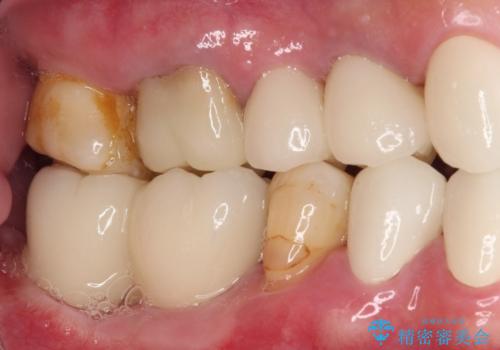

- 60歳を越え、黄ばんだ前歯をセラミッククラウンできれいな口元にしたいとのことで来院された患者様です。

診察したところ、前歯は反対咬合であり、その影響で抜歯が必要な奥歯があることが分かりました。

抜歯が必要な奥歯は、インプラント並びにブリッジにより補綴を行い、上下前歯は反対咬合を改善させるように補綴治療を行うこととしました。

健全な歯を削ってセラミッククラウンに置き換えることは、本来避けるべき治療と考えますが、今回は①患者様が60歳を越えていること、②要改善の咬合により抜歯が必要な奥歯があること、③反対咬合の前歯改善の手段としてセラミック治療が選択肢にあることなどから、全顎的なセラミック治療を行うこととしました。